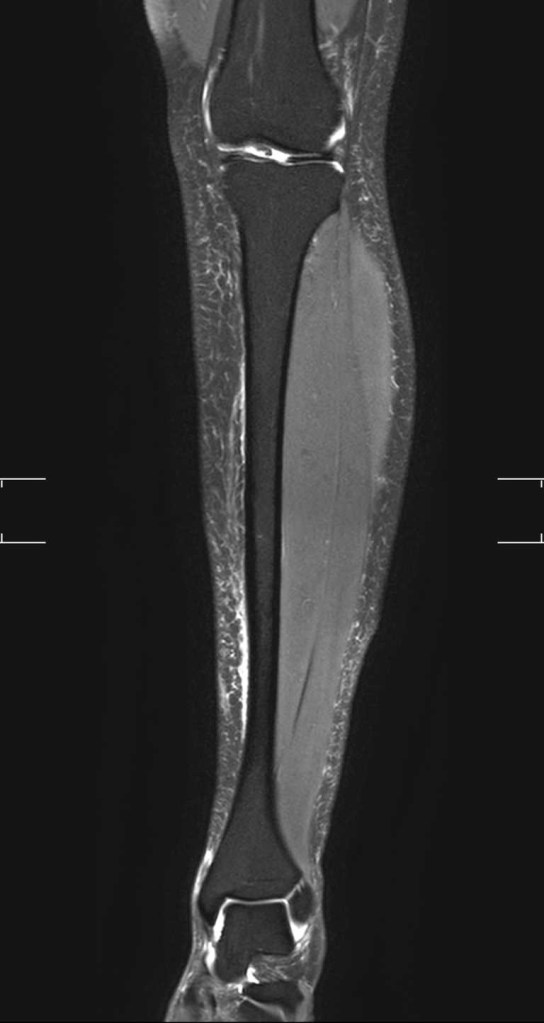

But it’s true. Unfortunately, I am currently injured with an anterior tibial stress injury. It’s a mild bone injury in a high risk spot on my leg. And means I’m spending a lot of time on the couch, tiny walks on crutches, and I won’t be running my first half marathon in 4 weeks.